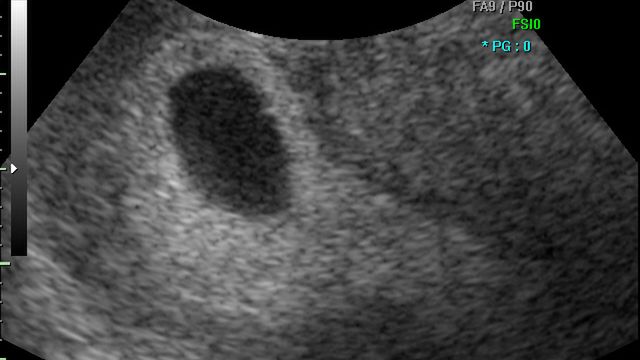

/ 3Płód w 9 tygodniu ciąży (bliźniaki jednokosmówkowe) - organy wewnętrzne

Serce dziecka posiada cztery komory, kształtują się organy wewnętrzne płodu